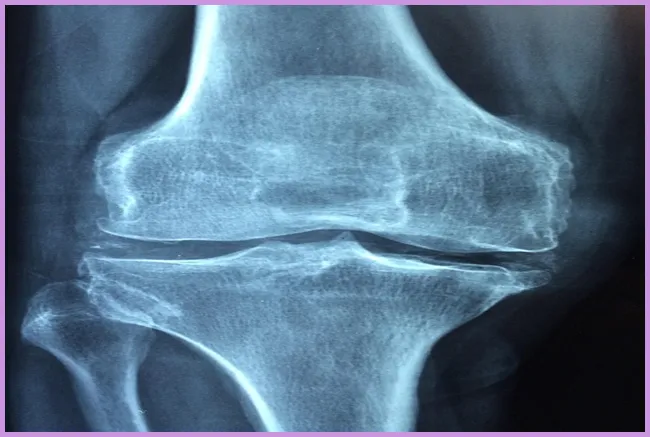

골밀도를 정기적으로 검사하는 것이 필요합니다. 특히 50세 이상의 여성분들은 첫 번째 검진이 중요합니다. 골밀도 검사는 비교적 간단하며, 골다공증의 조기 발견에 큰 도움이 됩니다. 골다공증 예방에 있어서 조기 진단과 치료는 미래의 골절과 부상의 위험을 크게 줄일 수 있습니다.

전문의와 상담을 통해 개인의 뼈 건강 상태를 점검받는 것이 좋습니다.이 검사는 뼈 건강을 모니터링하고 적절한 예방책을 마련하는 데 도움을 줍니다.